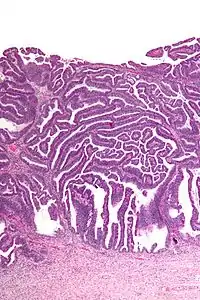

| Micrograph of a villoglandular adenocarcinoma the cervix. H&E stain. | |

The name of the lesion describes it microscopic appearance. It has nipple-like structures with fibrovascular cores (papillae) that are long in relation to their width (villus-like), which are covered with a glandular pseudostratified columnar epithelium.

Very low magnification

Very low magnification Intermediate magnification